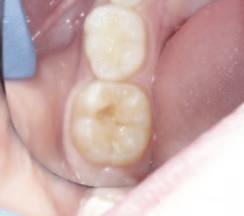

The occlusal surfaces of the first permanent molars are one of the sites most commonly affected by dental caries development. This is due primarily to their early eruption, posterior location, immature enamel, and anatomic pits and fissures, which facilitate the development of a bacterial biofilm. Sealing these pits and fissures can prevent biofilm development and thus form part of a comprehensive caries prevention programme. Current guidelines recommend caries risk assessment for all children and the placement of resinbased fissure sealants on the first and second permanent molars of those deemed high caries risk.1

While highly effective, resin-based sealants have several limitations. Firstly, resinbased dental materials are hydrophobic, meaning effective moisture control is very important. This can be difficult in cases of poor patient co-operation or when dealing with partially erupted teeth. It has been found that permanent molars can take up to 34 months to erupt fully.2 Therefore, teeth may be exposed to the oral environment unprotected for nearly three years. As caries development is most likely in the first few years following eruption, this represents a significant risk.

In the case of molar incisor hypomineralisation (MIH), altered enamel morphology may prohibit the successful bonding of resin-based materials. In addition, hypersensitivity can prevent completion of etching, rinsing and drying without local anaesthetic. Furthermore, if there is evidence of post-eruptive breakdown, resin-based sealants may be contra-indicated.2

Alternatives to resin-based sealants

Glass ionomer (GI) sealants can be utilised when a resin-based sealant is indicated but cannot be placed due to poor moisture control, resulting from either inadequate tooth eruption or poor patient co-operation. GI is hydrophilic, making it more compatible with the oral environment. Another significant advantage of GI sealants is their action as a fluoride reservoir, aiding in the remineralisation of enamel.

Finally, in instances of MIH, GI may be considered the first-line sealant material (Figure 1).3 Placing a resin-based sealant on a sensitive tooth may be distressing for a child and may increase the risk of treatment-induced anxiety. Even though the retention rates for GI sealants are reduced compared to those of resin-based sealants, studies have shown that small amounts of material remain in the pits and fissures even after the sealants appear to have debonded.4

Process of fissure sealing with high-viscosity glass ionomer using the atraumatic restorative treatment technique3

1. Employ a four-handed technique where possible.

2. Achieve isolation using cotton wool rolls (Figure 2).

3. Dislodge plaque and debris with a probe and clean the surfaces using wet cotton pellets or a toothbrush.

4. Apply an enamel conditioner (e.g., 20% polyacrylic acid such as GC Cavity Conditioner) for 10 seconds (Figure 3).

5. Remove the conditioner and dry the surface, using wet, and then dry, cotton pellets. Care should be taken not to desiccate the enamel.

6. Apply a high-viscosity GI material, such as GC Fuji IX, directly onto the tooth using an applicator gun, dental instrument, or a gloved finger lubricated with petroleum jelly (Figure 4a).

7. Manipulate the material into the pits and fissures using finger pressure (Figure 4b).

8. Remove finger in a lateral direction after 10-15 seconds.

9. Remove excess with an instrument such as an excavator, and adjust occlusion as required.

10. Place a new layer of petroleum jelly and allow the material to set fully while maintaining isolation (Figure 5).

FIGURE 1: Hypomineralised mandibular right first permanent molar with early post-eruptive breakdown – suitable for a GI sealant. Natasha Lemasney BA BDentSc MFD RCSI MSc Senior House Officer, Paediatric Dentistry Cork University Dental School and Hospital Siobhán Lucey BDS NUI MFDS